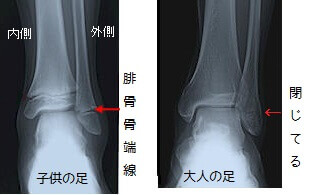

足首を内側に曲げ、外くるぶしにストレスをかけて左右の足を撮影します。

レントゲン写真を見せられながら説明を受けました。

『ほら、こっちの方が開いてるでしょ。骨折だね。』

腓骨骨端線離開ということで、外くるぶしに子供のうちだけある軟骨(骨端線)を骨折しているとのこと。

大人になると完全に閉じてなくなってしまう、いわゆる『成長軟骨』というもの。